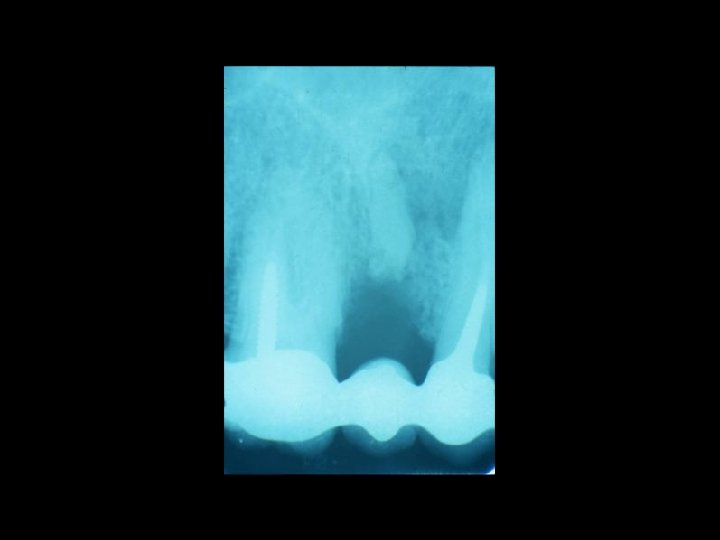

Il contenzioso PRINCIPALI AMBITI Ø Ø Ø La diagnosi La chirurgia orale La terapia conservativa Il trattamento delle anomalie dento-scheletriche La riabilitazione protesica

Responsabilità Ø Restauro della corona del dente Ø Trattamenti radicolari